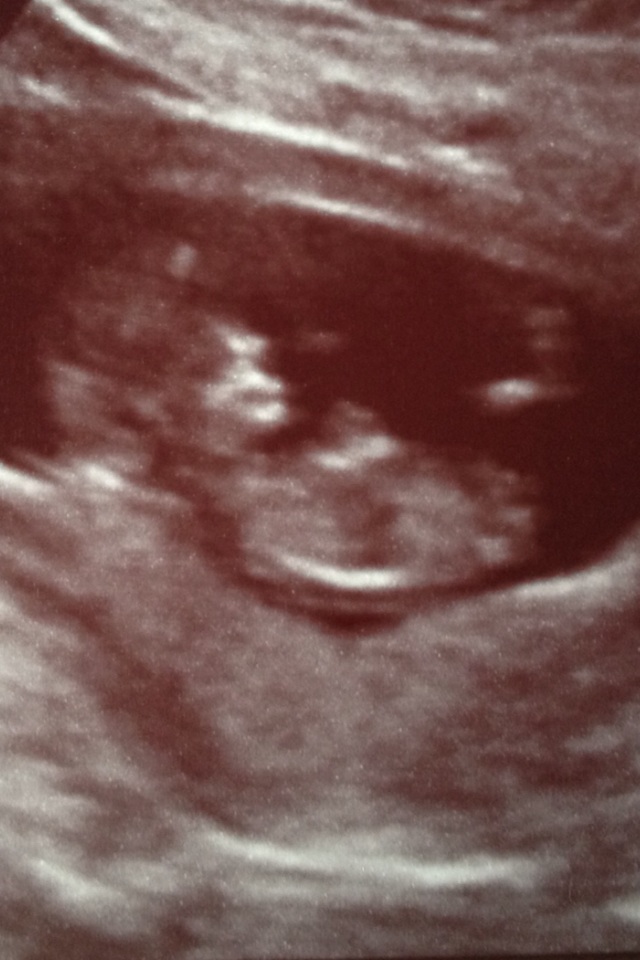

I had my NT scan today. Scan went well though I almost fainted from the finger prick (though had zero issue with the arm blood draw for the Panorama test). Praying for good blood tests results in the next two weeks. New ultrasound pics! So excited baby looks like a baby. So much growth since my last US at nearly 9 weeks.